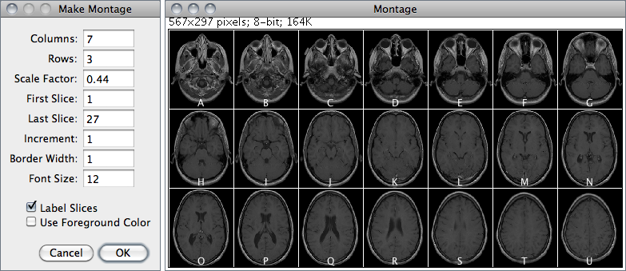

Imagej User Guide Ij 146r Image Menu

Calculation Of Brain Atrophy Using Computed Tomography And A

3d Processing And Analysis With Imagej

3d Viewing Of Ct Mrt Data Using Fiji Imagej